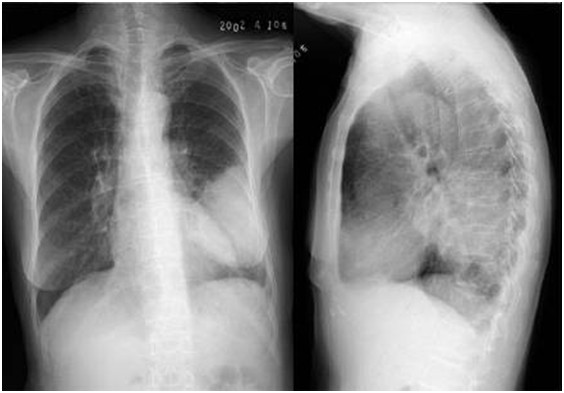

04卷-3.病史:男性,53歲,咳嗽、體重減輕4個(gè)月。診斷(本題滿(mǎn)分2.00分)

本題答案:C

題目解析:

【該題針對(duì)“ X線-肺癌 ”知識(shí)點(diǎn)進(jìn)行考核】